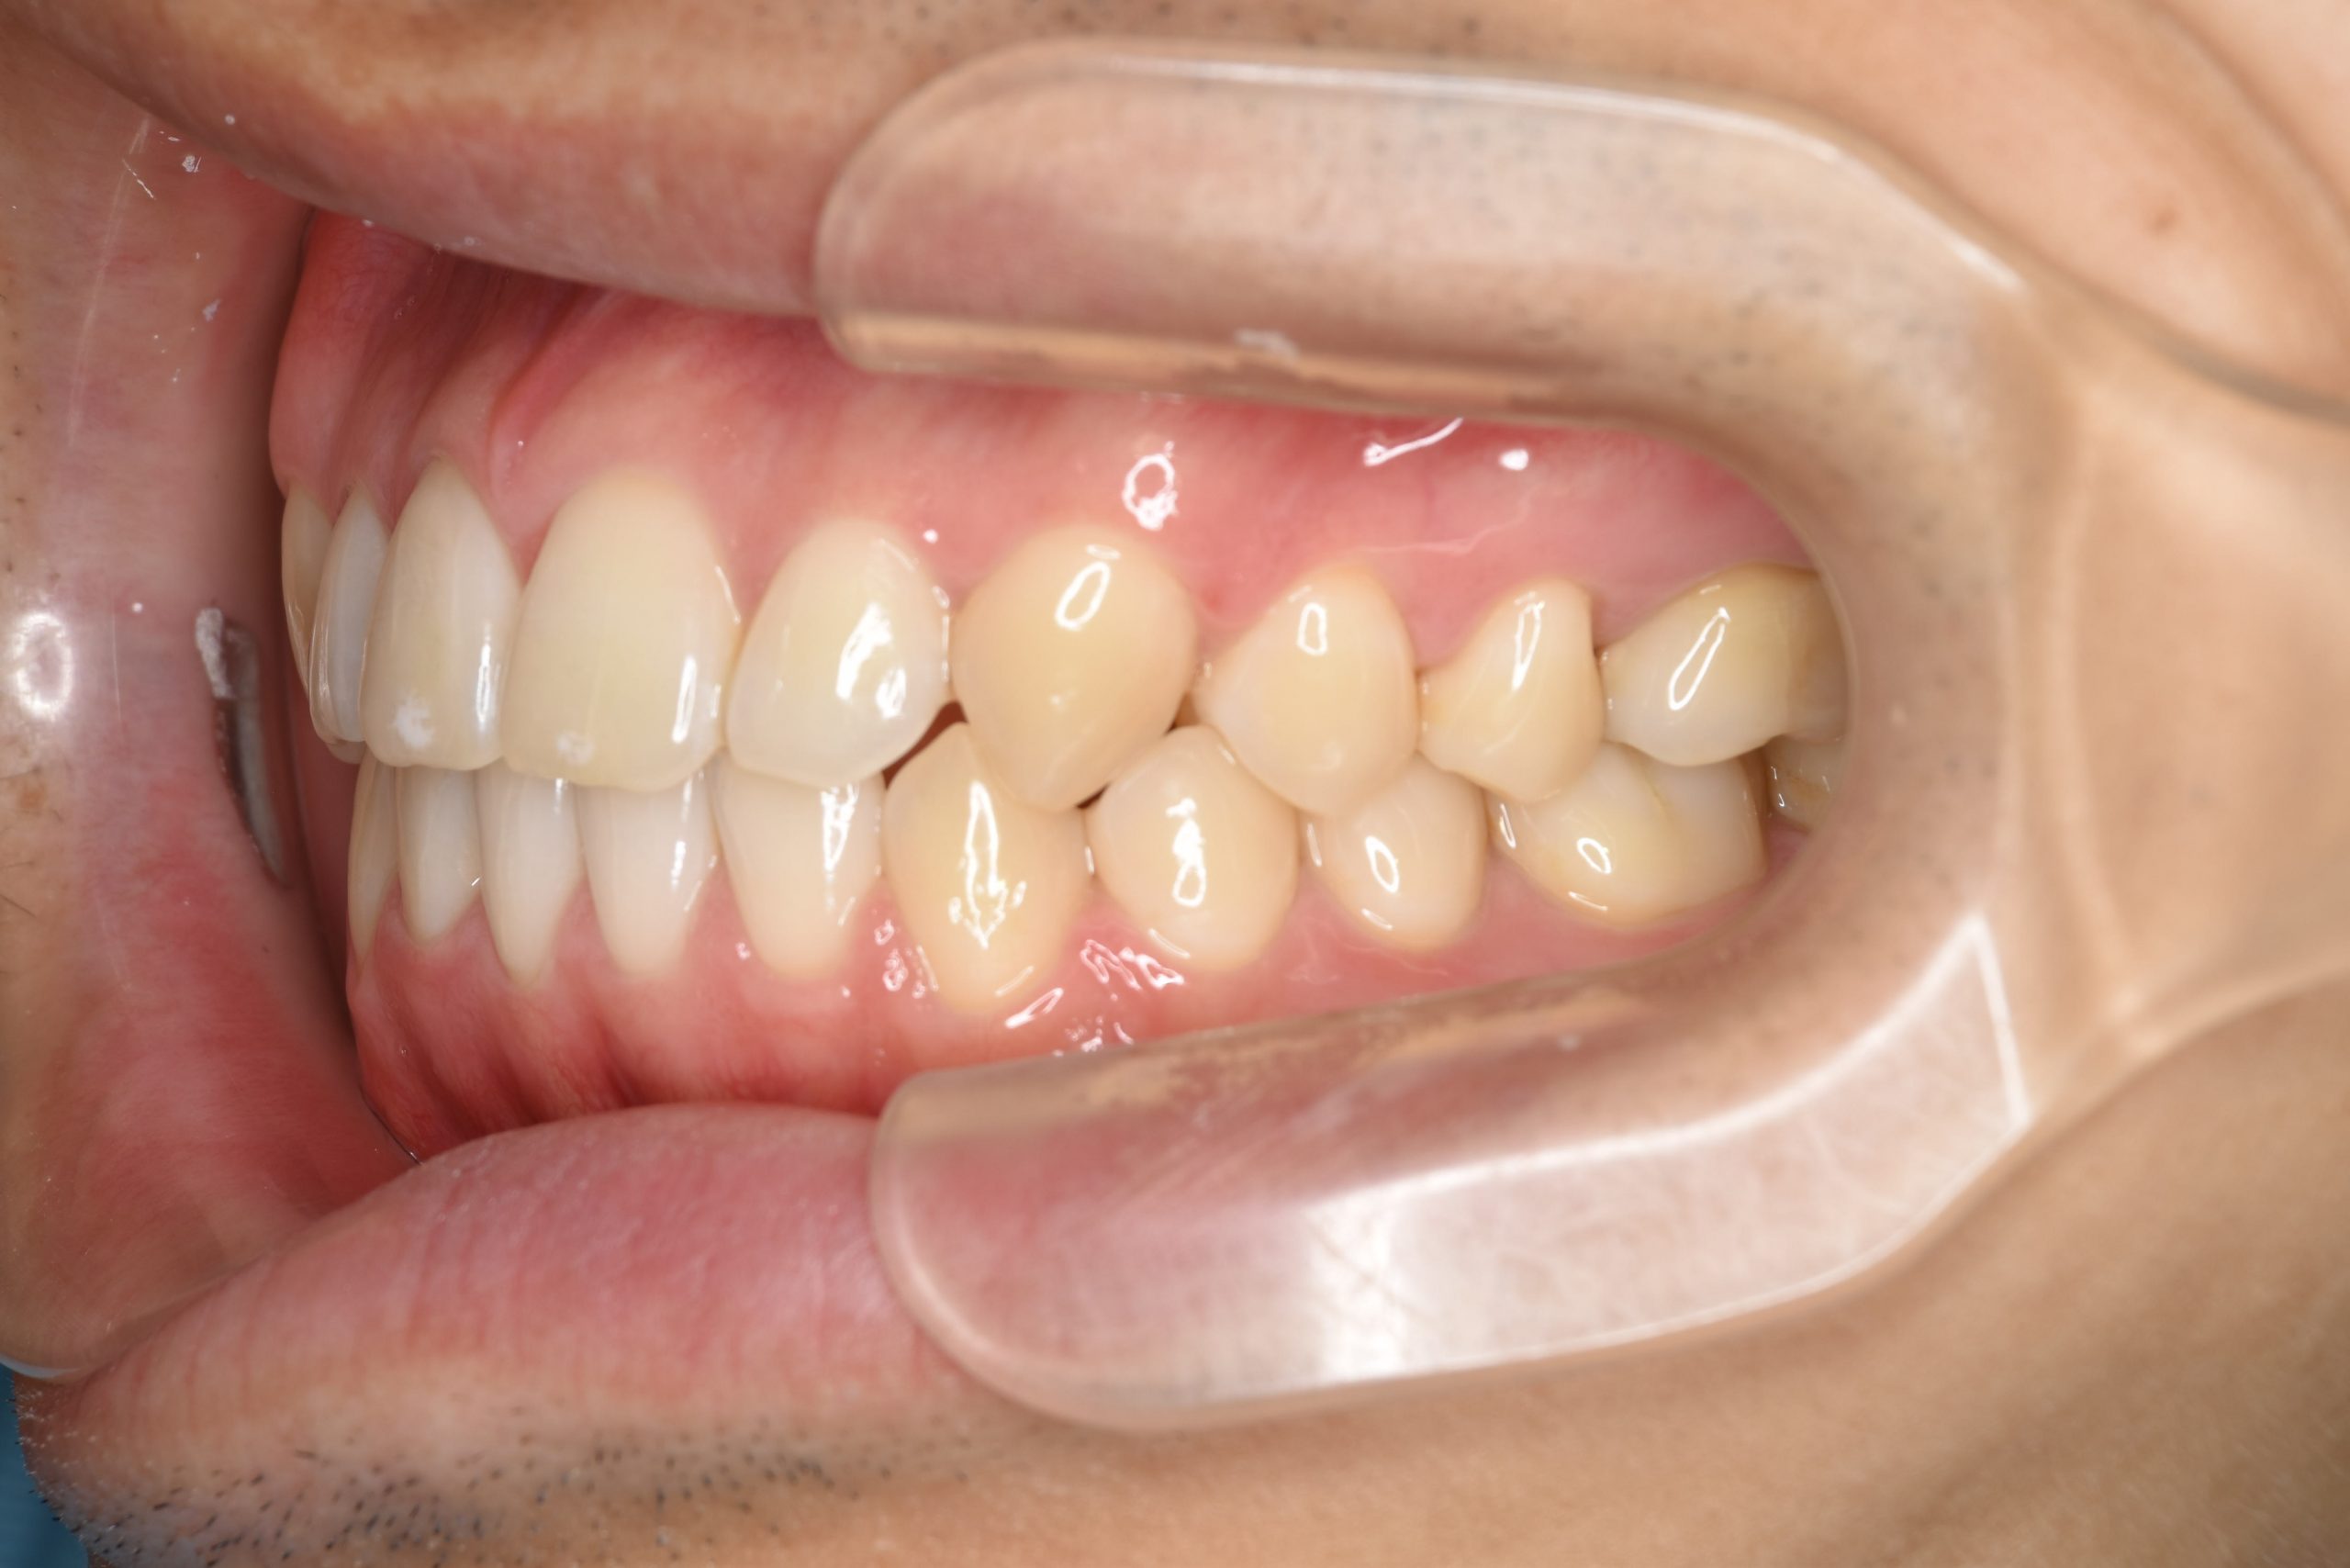

アフター

ワイヤー矯正治療|症例_495

施術内容 MSEと下顎リンガルアーチを用いて上下顎骨を拡大した。

その後マルチブラケット装置とミニインプラントを用いて

非抜歯で歯牙を配列し、良好な咬合を獲得した。

下口唇の突出感と鼻閉症状は改善した。